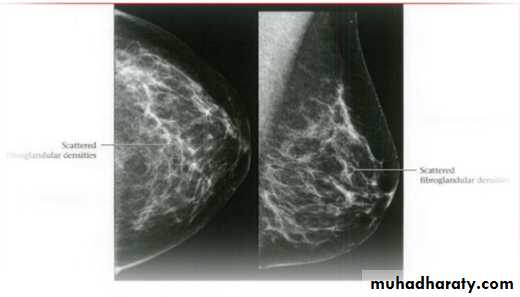

Breast density & who can U detect a mass lesion

Your mammogram report must take in consideration & assessment the breast density. Breast density is based on how fibrous and glandular tissue tissues are distributed in your breast, vs. how much of your breast is made up fatty tissue.

Dense breasts are not abnormal, but they are linked to a higher risk of breast cancer. We know that dense breast tissue can make it harder to find cancers on a mammogram. Still experts do not agree what other tests, if any, should be done in addition to mammograms in women with dense breasts who aren’t in a high-risk group (based on gene mutations, breast cancer in the family, or other factors